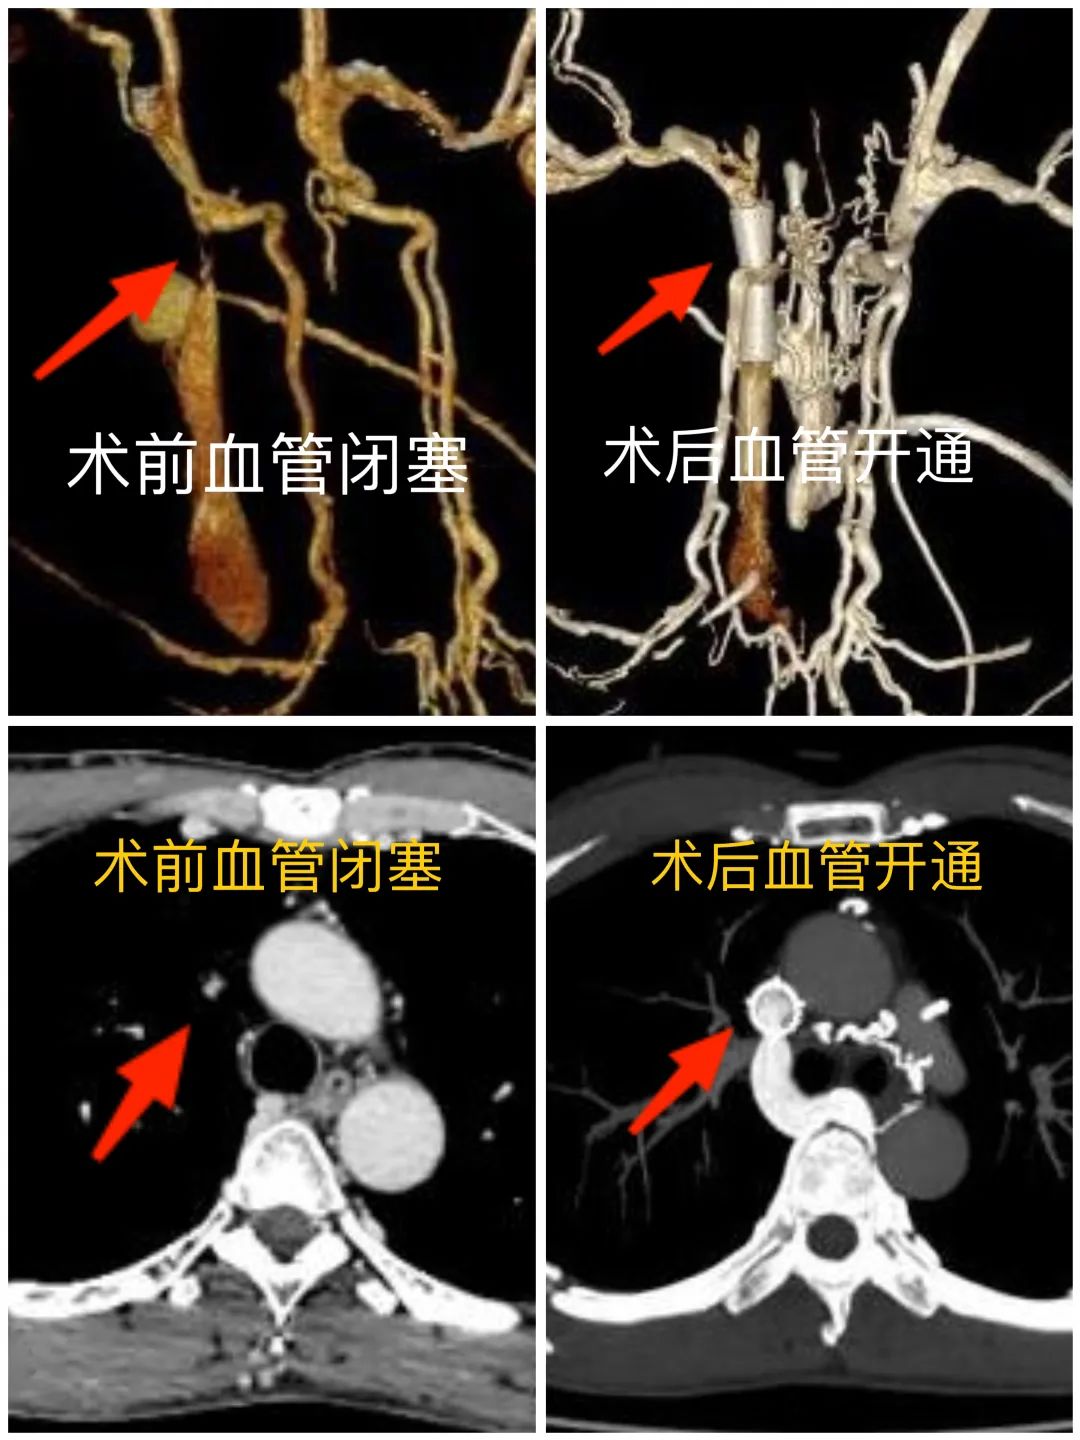

一检查问题不小,上腔静脉上段闭塞,伴奇静脉、胸廓内静脉、胸壁静脉曲张,左侧头臂静脉汇入异常,伴纵膈静脉侧支血管形成...... 结果明确,8 年的谜团也终于解开了。老张得了上腔静脉综合征。

「我们完善检查发现,老张上腔静脉处病变情况确实复杂,上腔静脉一段已经完全堵实,要想开通,手术难度不小,就像『拿针钻墙』,这个『墙』还是个靠近心脏的『危墙』,操作必须小心。」

在于主任的指导下,侯军、姜海军副主任医师为老张做了【上腔静脉支架球囊扩张+支架植入术】。

术中,通过造影可见,老张的血管迂曲严重,走向分支错综复杂,导丝找到「堵点」后反复尝试探行,毫厘之间小心翼翼地变化角度位置,寻找「突破点」,终于扩开了约 3 厘米长的闭塞段,并成功植入支架,顺利地为血流钻出一条畅行通道。

术后老张各种不适症状明显缓解,很快康复出院。日常生活不受影响,困扰老张近 10 年的怪病一解决,曾经的农活好手又回来了。